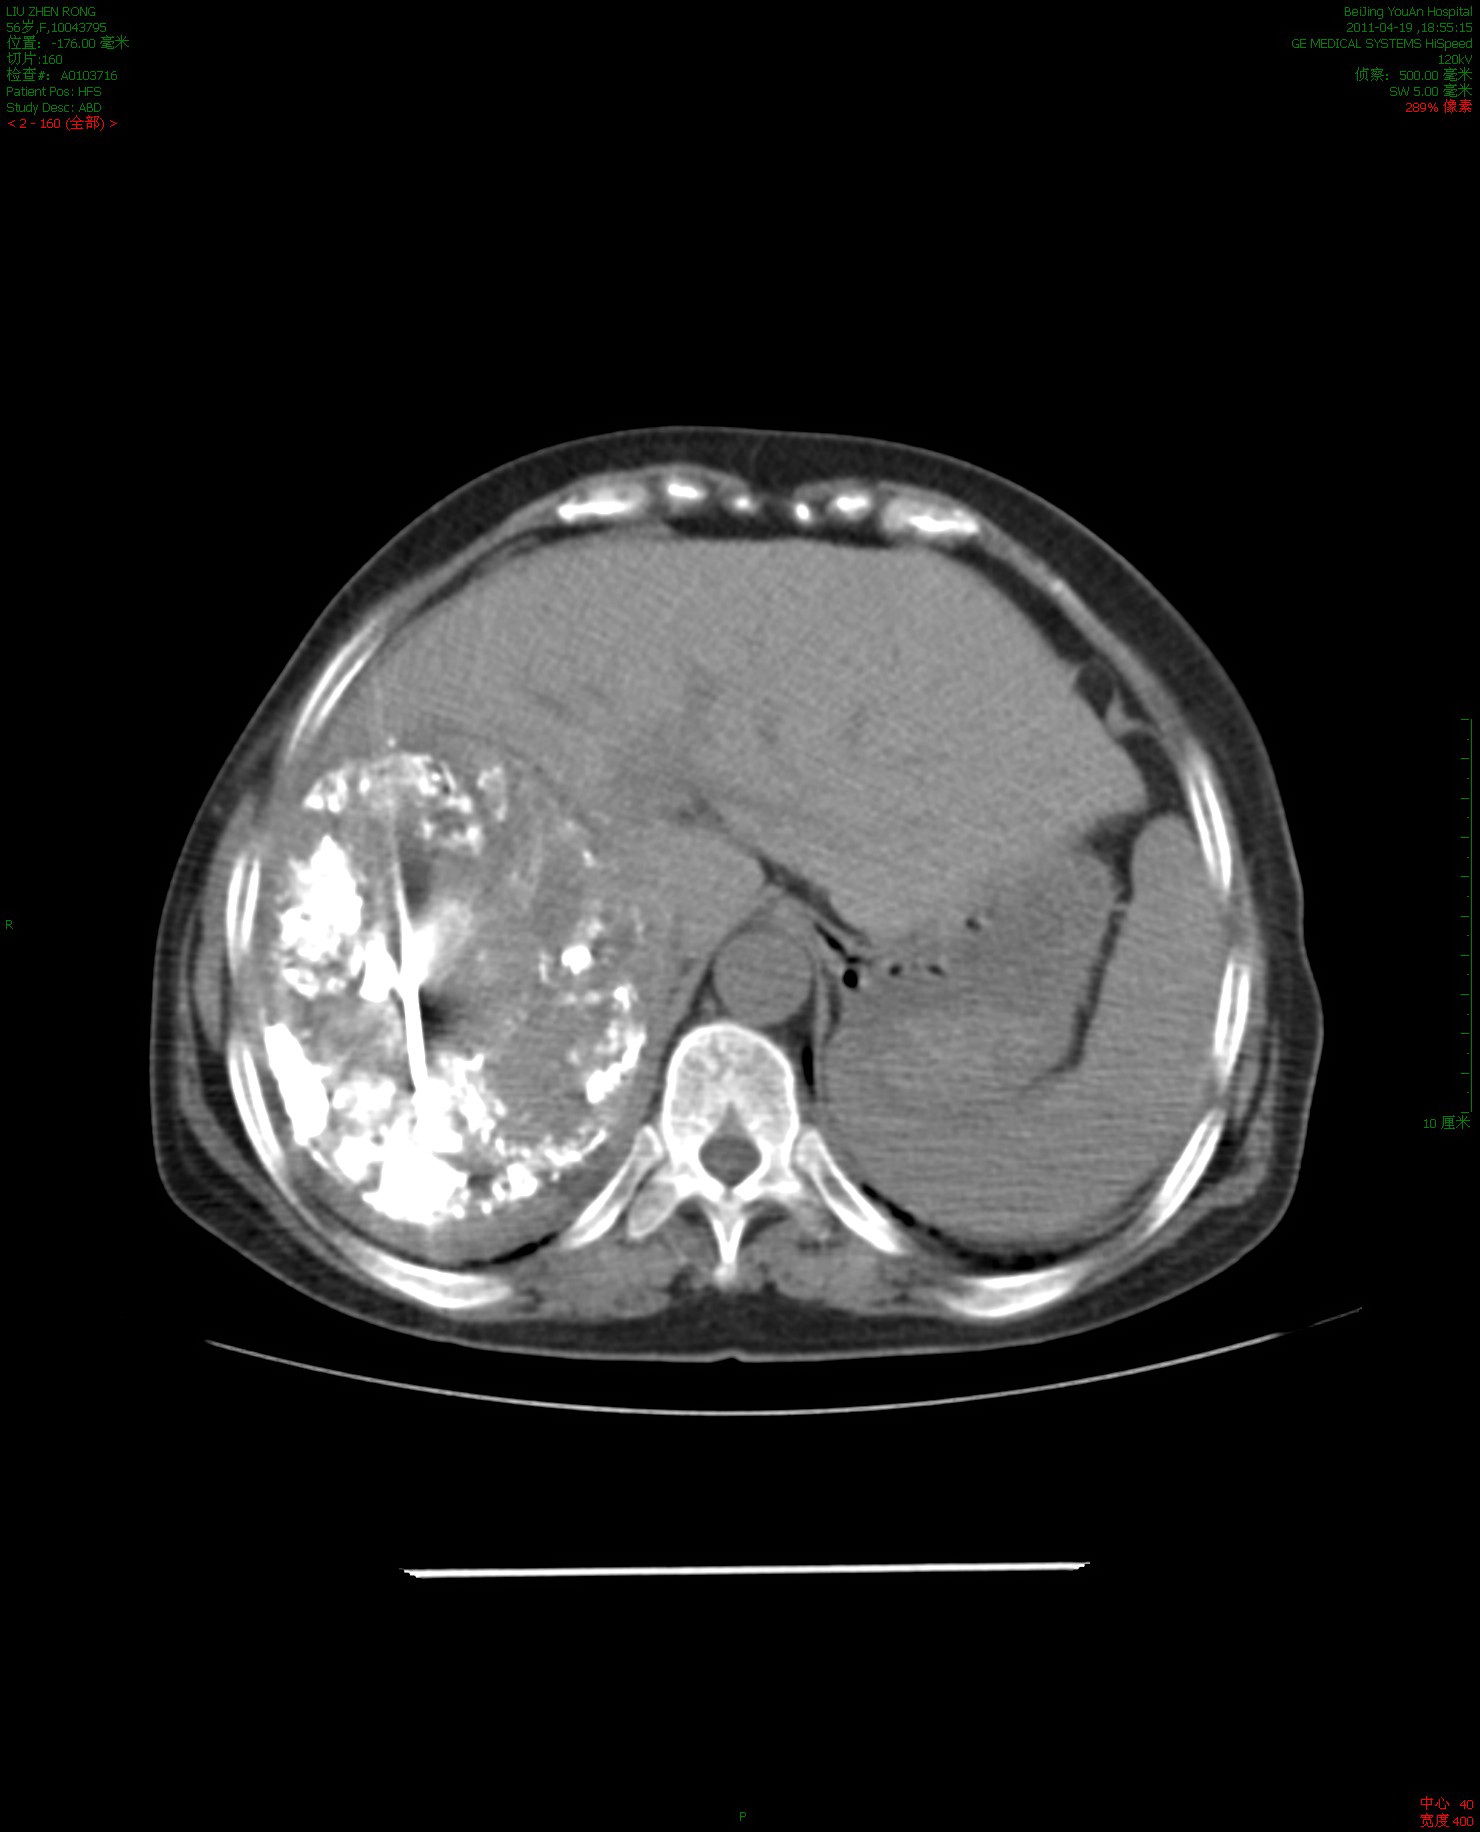

消融肿瘤40%-50%微创治疗前增强ct56岁的肝癌晚期患者,女性

图片尺寸1480x1832